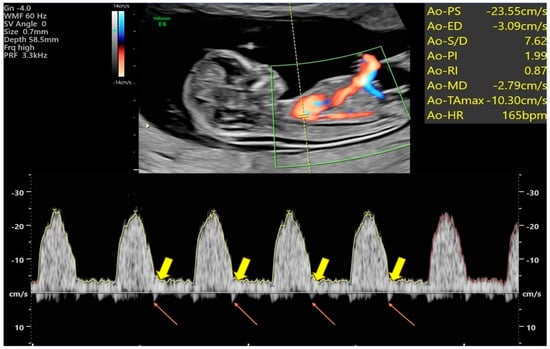

2.3. Assessment of Blood Flow Velocity Waveforms and Indices within the Fetal Aorta